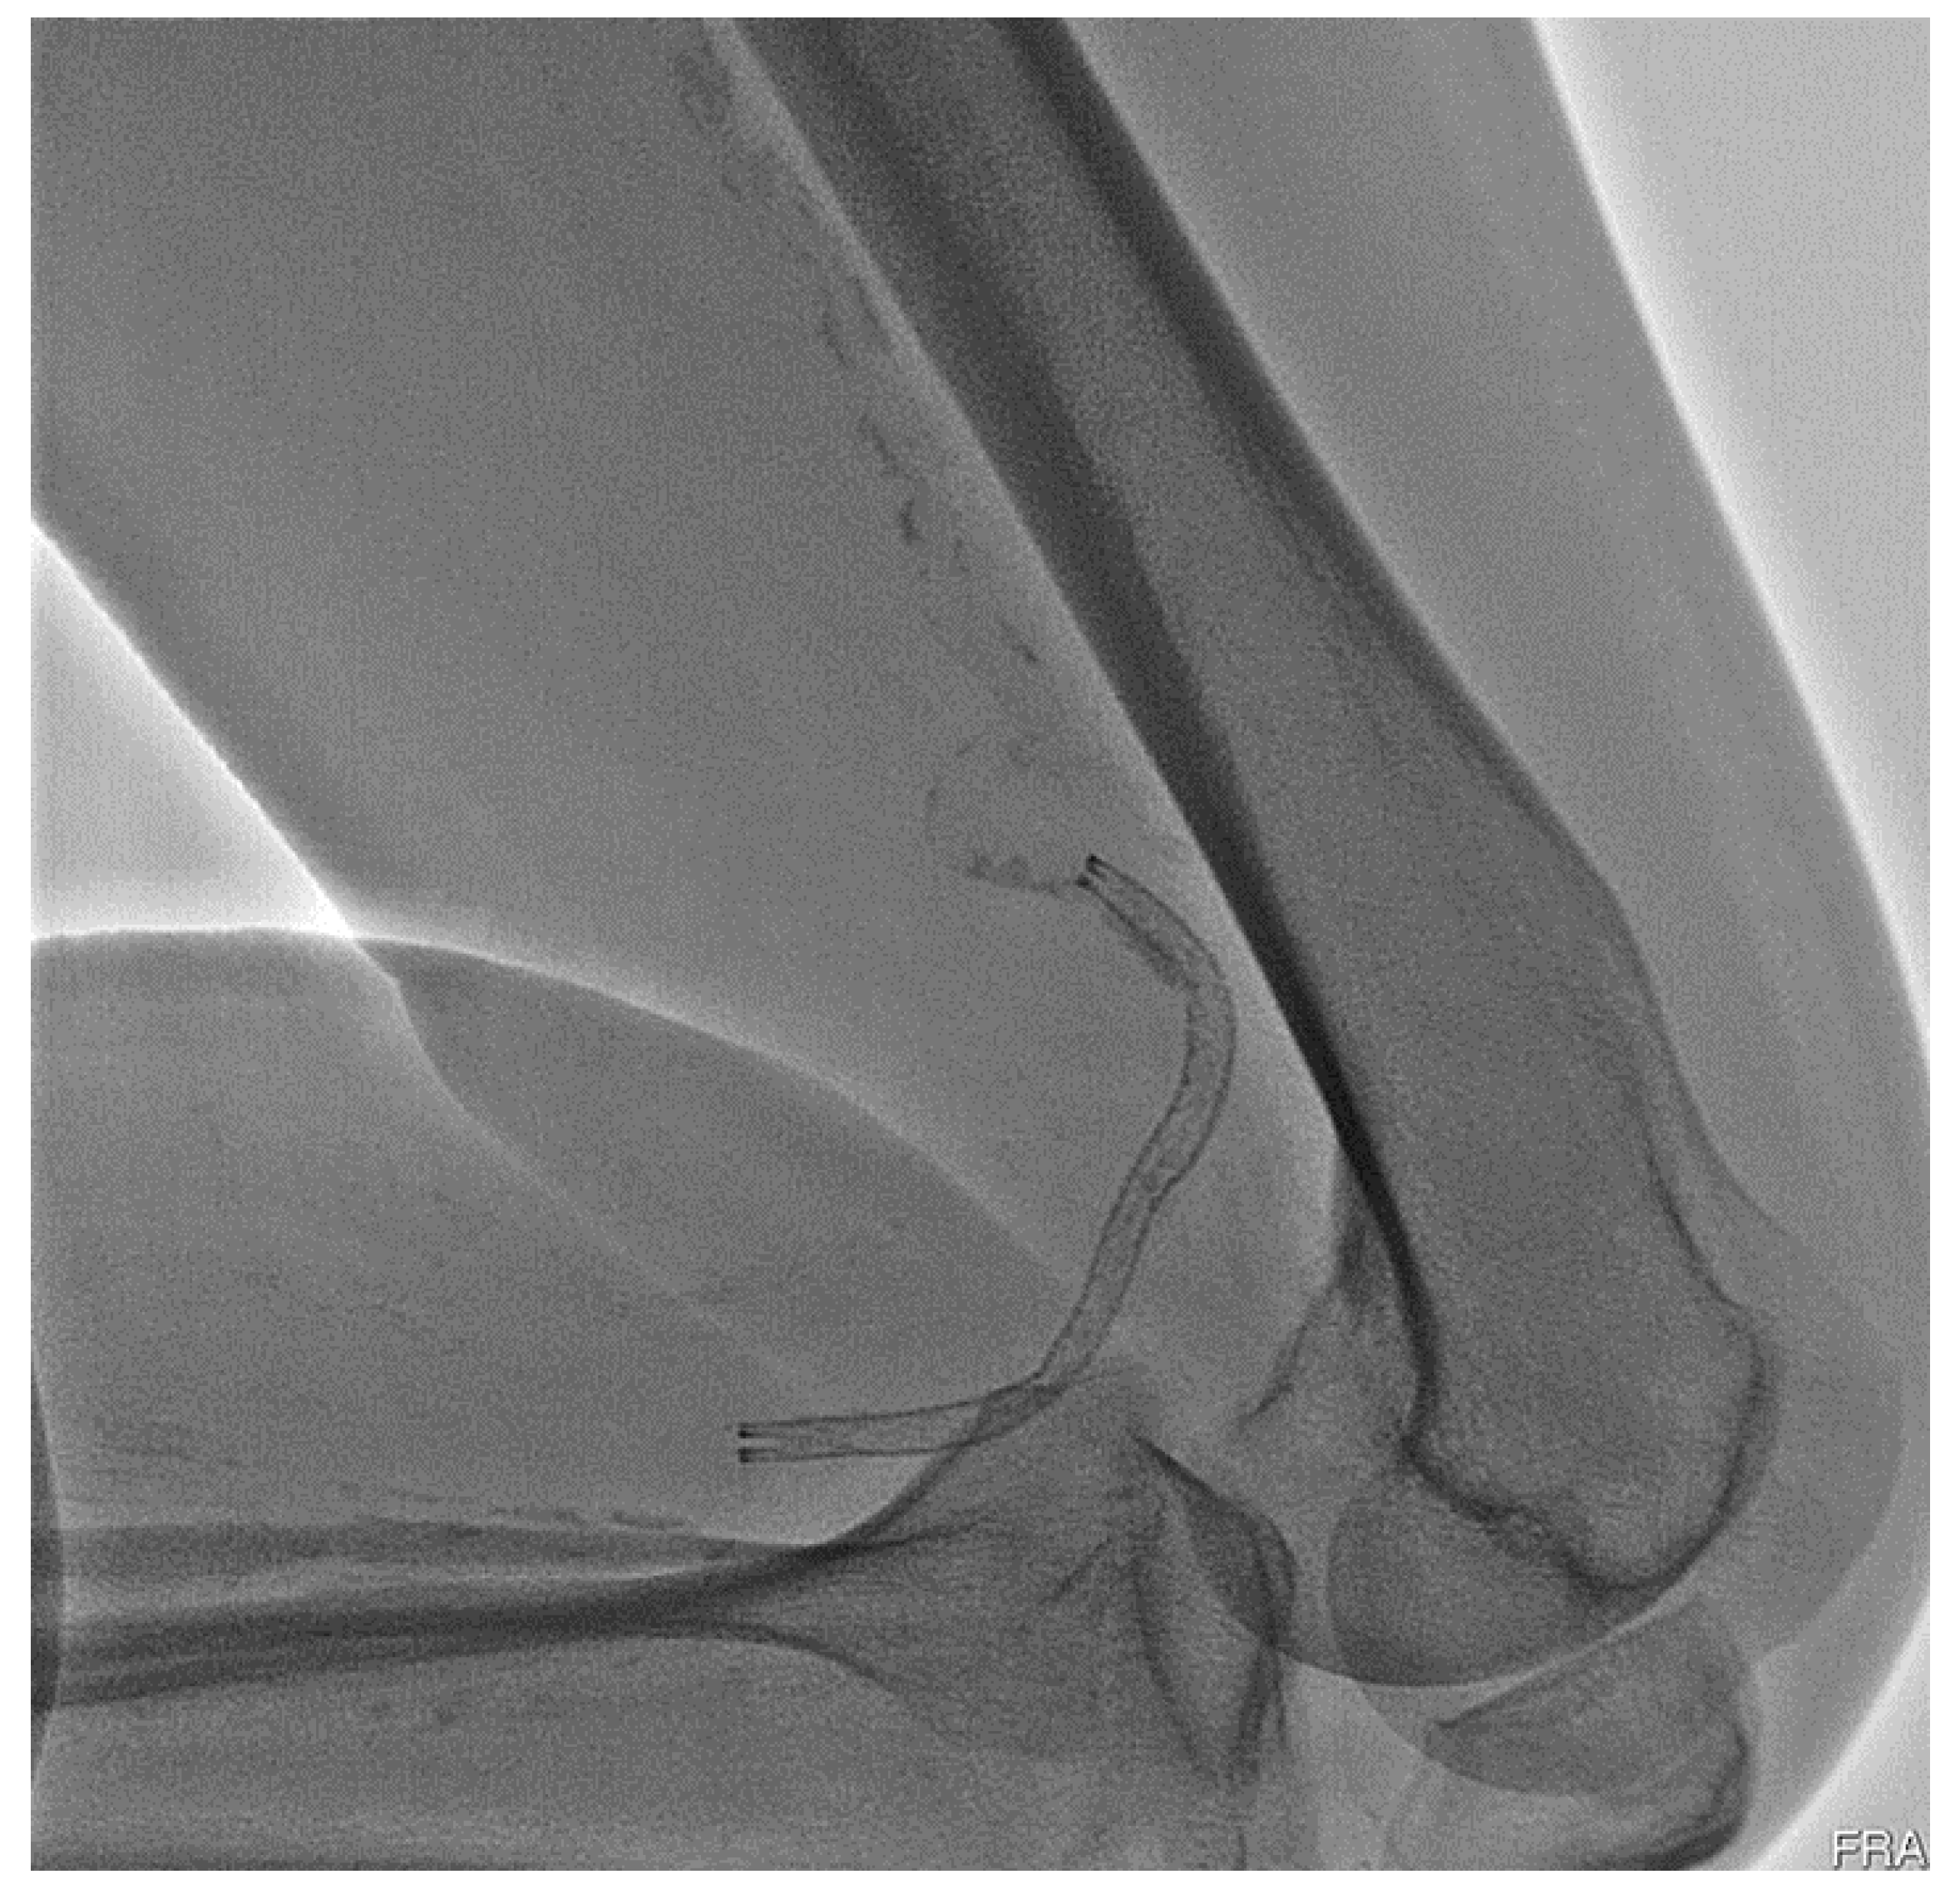

However, peripheral stent could fracture from cyclic loadings due to blood pressures and our body activities after surgery. Such repeated movements continue to oscillate the stent, leading to the risk of fatigue fracture which may cause radial support loss to the arterial wall, in-stent restenosis, thrombus formation, or arterial perforation by sharp strut protrusion [3,4,5]. Partial or complete stent fatigue fractures have been reported in the cases of lower limbs with high fracture rates [6,7,8,9,10]. Peripheral stent fatigue fracture is a known complication of peripheral intervention and is related to increased re-occlusion risk of the treated artery. It has attracted many attentions in the past decades and, therefore, stent fatigue life is a key performance issue for many contemporary peripheral stent designs. Figure 1 shows the deformed shape of an implanted peripheral stent subjected to complex loading conditions when a patient bent his knee.

Figure 1.

Deformed shape of a peripheral stent inside a bent patient knee.